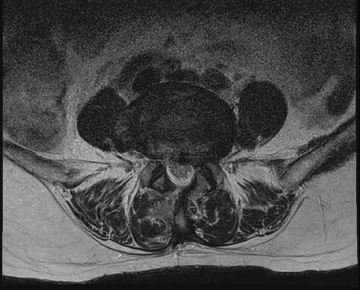

요추 협착증 수술 전·후

2022.08.08

2022.08.19

ㆍ환자 동의를 받은 자료이며, 이미지 사진은 실물과 다를 수 있습니다.

ㆍ모든 자료는 새움병원 자료입니다.